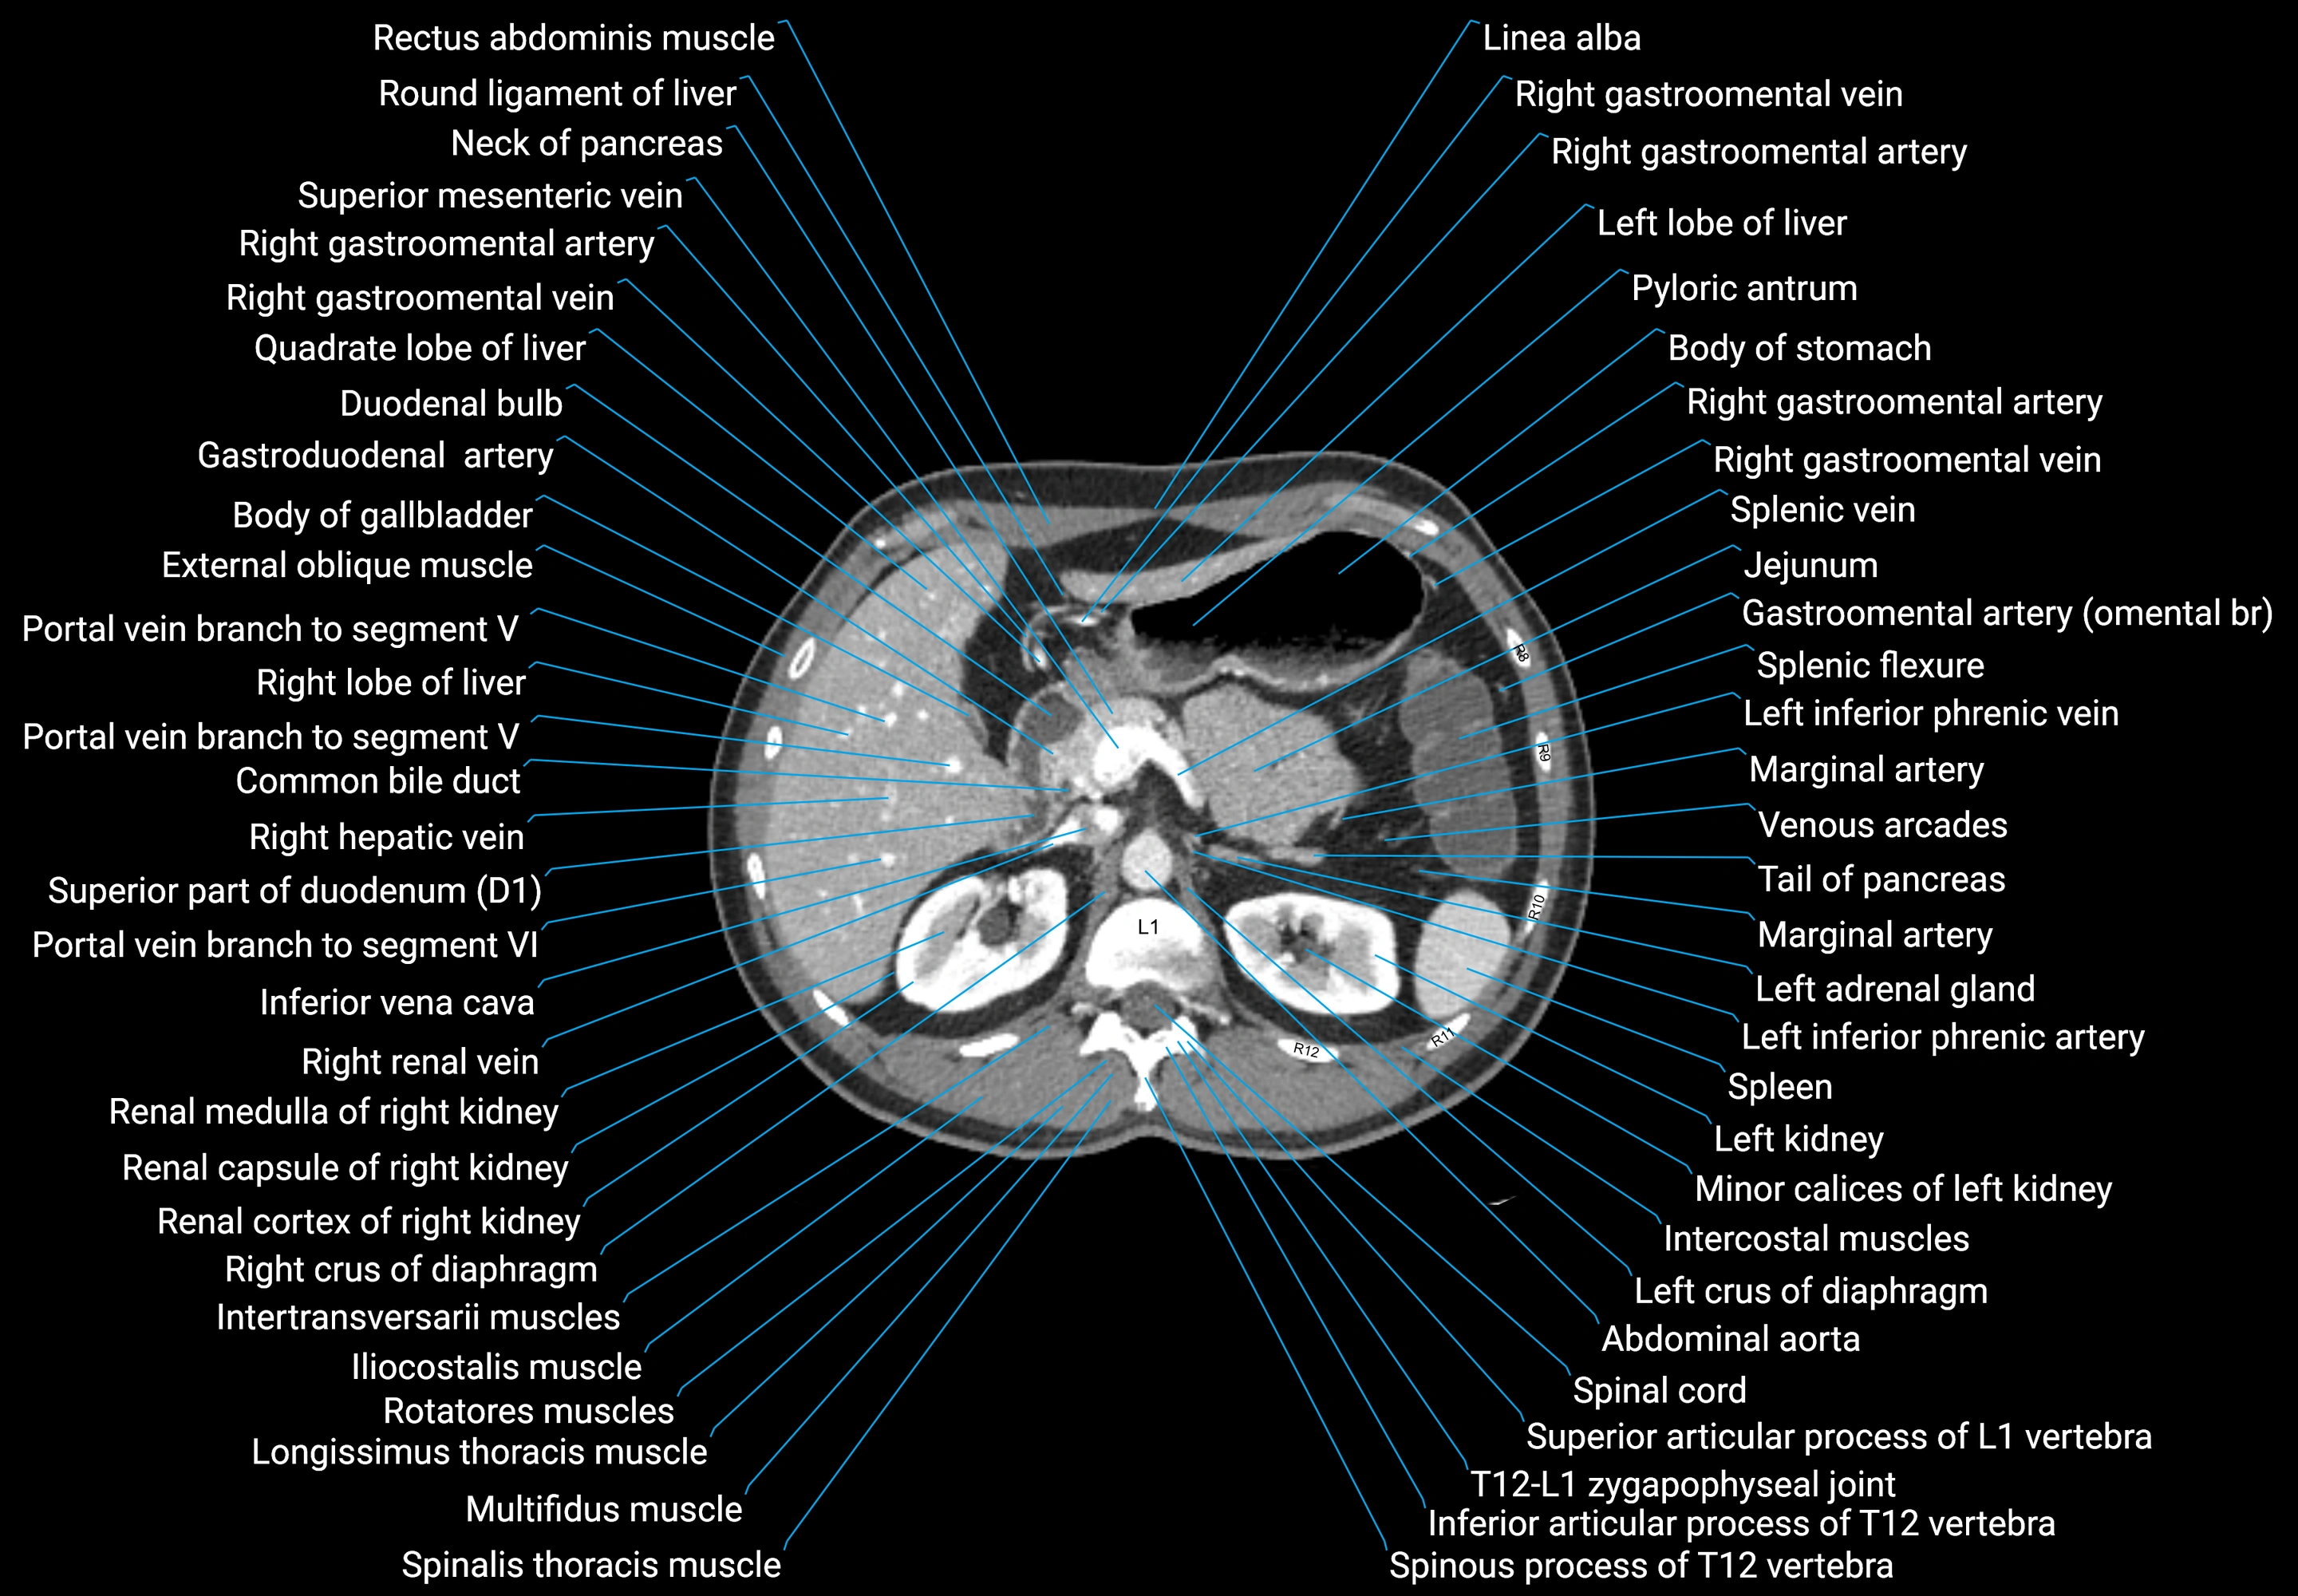

CT images